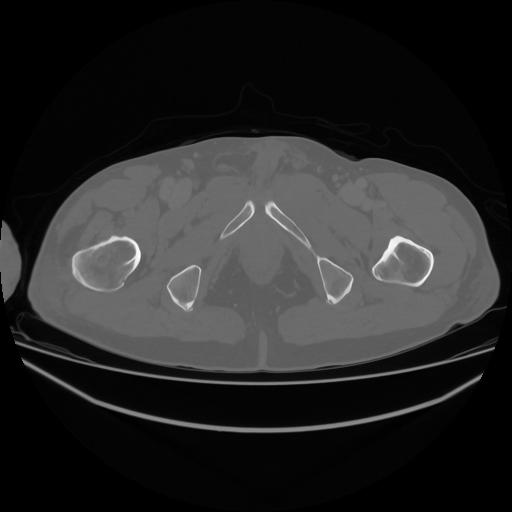

5 CUERPO,CE,Vol,1.0,CUERPO,,